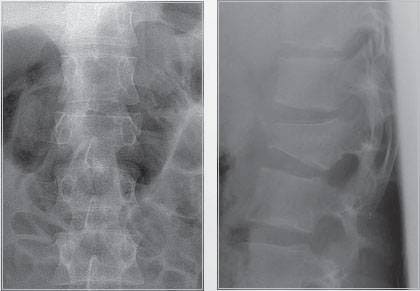

Перелом тела L2.

Передний спондилодез L1-L3 с замещением тела L2 имплантом Obelisc.